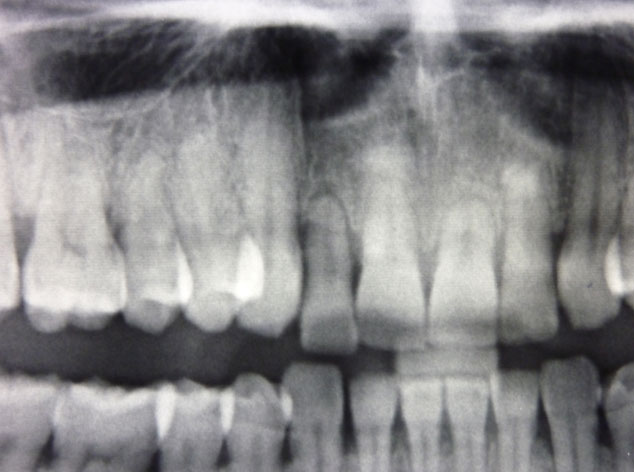

En estos casos han sido tratados con la filosofía de all-at-once, en la

misma sesión: